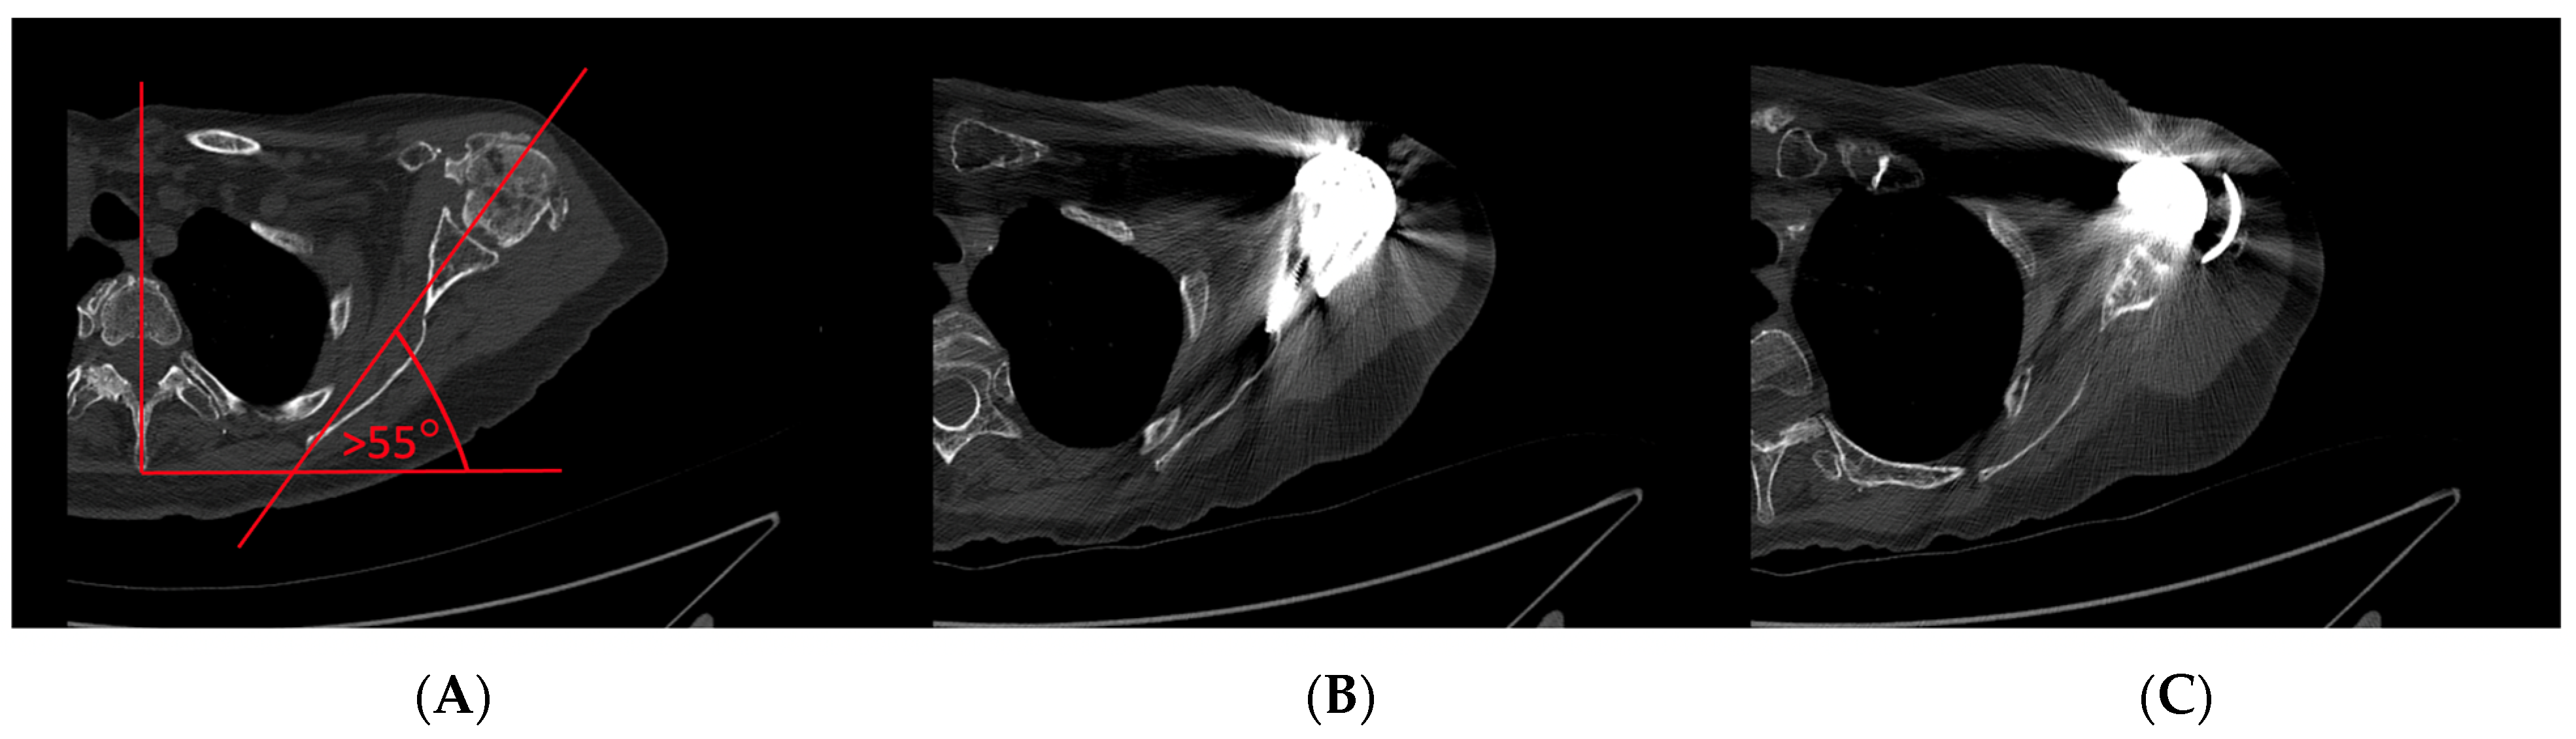

2. Conservation of Sufficient Subacromial and Coracohumeral Space